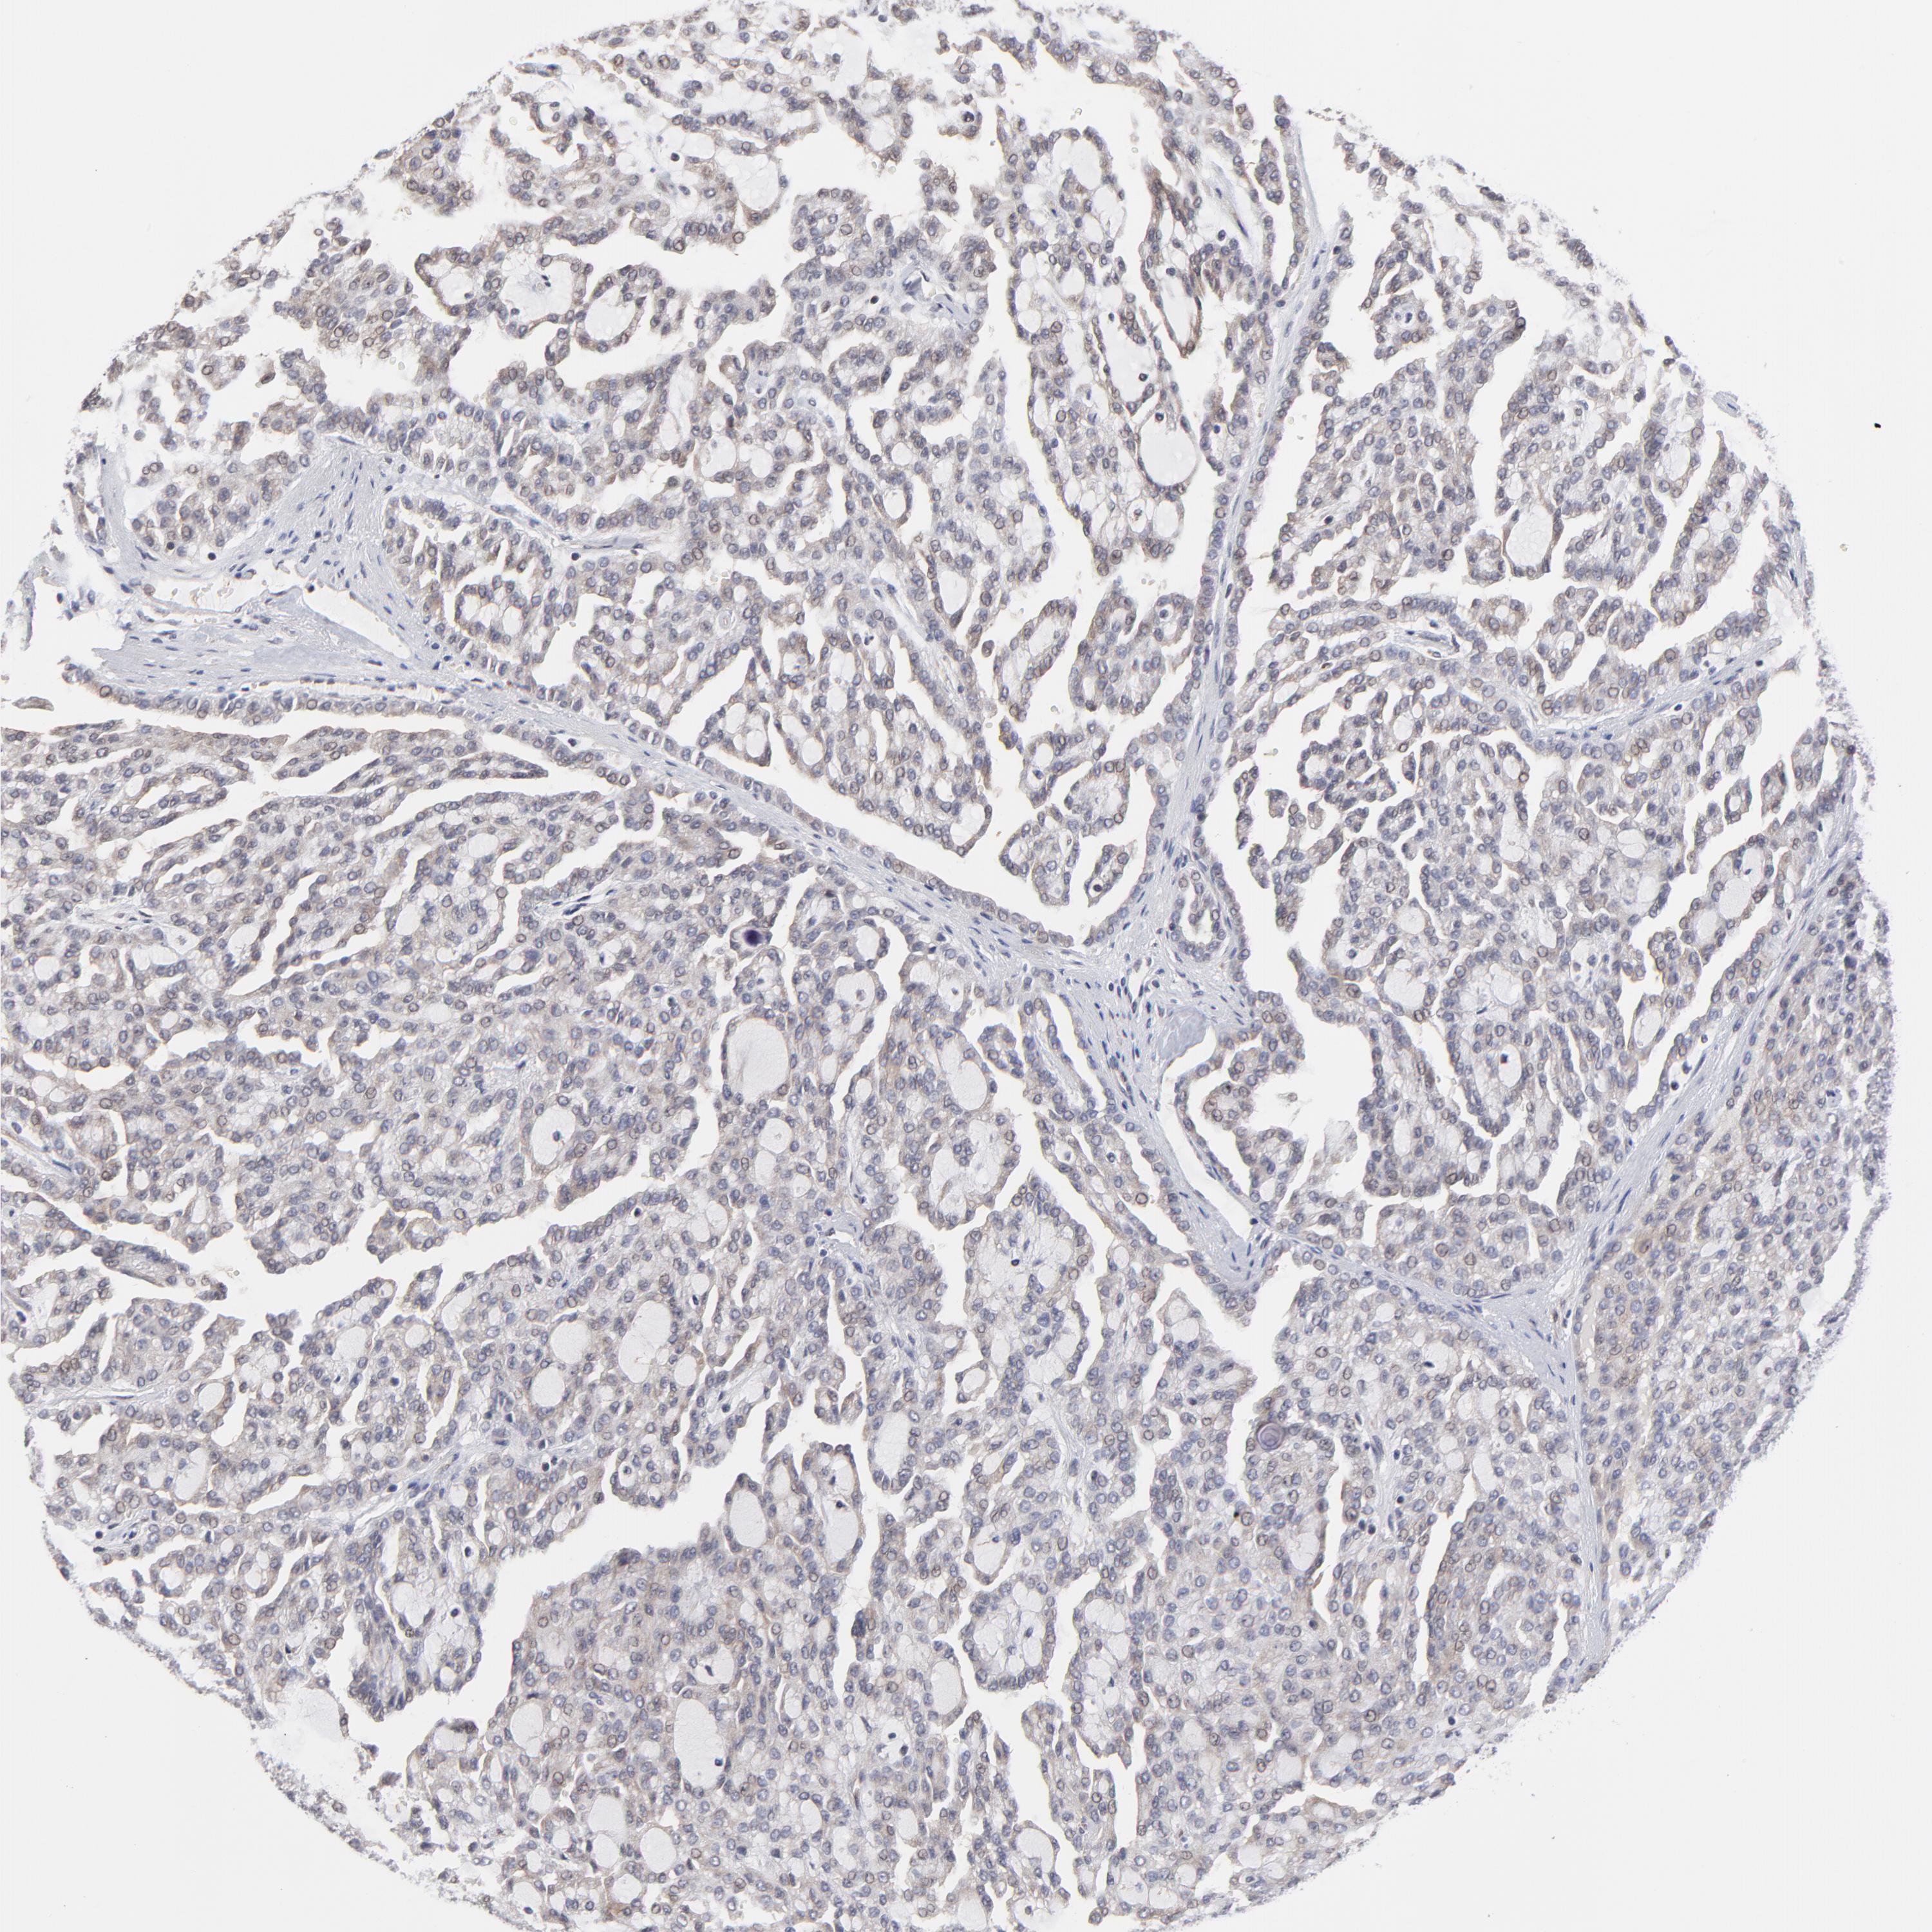

ZNF157

CANCER RENAL CANCER Show tissue menu

Renal cancer

Kidney renal clear cell carcinoma